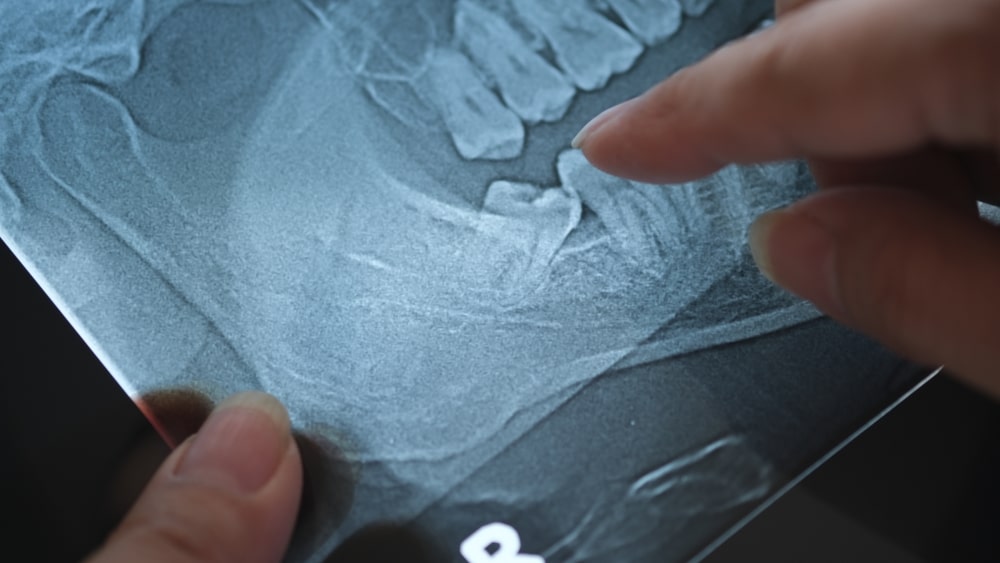

Tam gömülü dişler, diş eti ve çene kemiği dokusunun altında tamamen saklı kalmış, ağız içinde görünmeyen dişlerdir. Bu tip dişler genellikle röntgen çekimiyle tespit edilir. Tamamen gömülü kalmış dişler, uzun vadede çevresindeki dişlerde baskı oluşturabilir, kist oluşumuna veya çene kemiğinde bozulmalara yol açabilir. Bu nedenle çoğu zaman cerrahi müdahale ile çıkarılması gerekir.